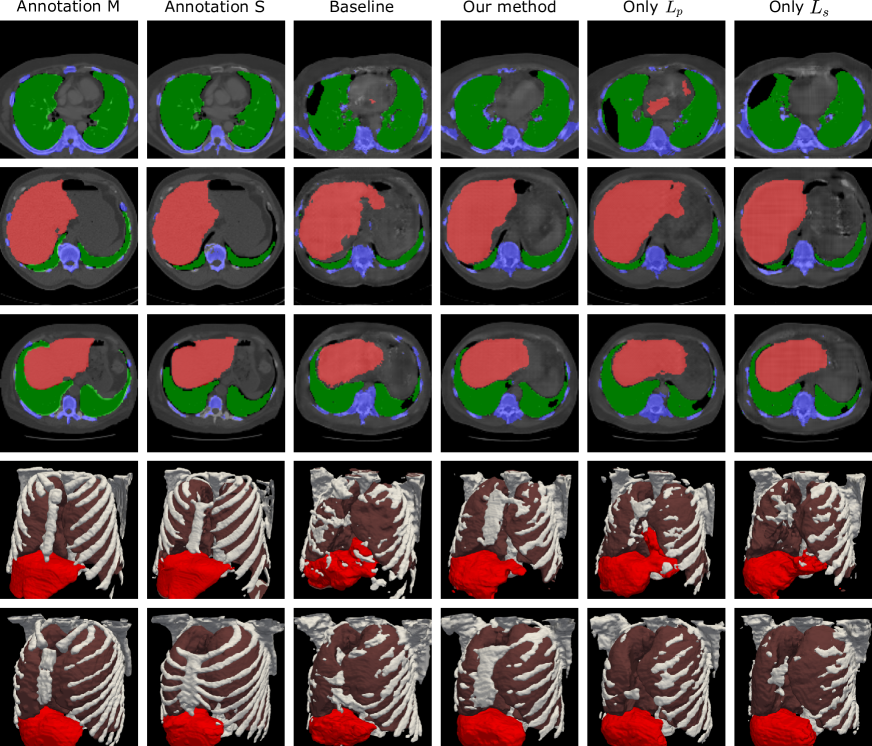

Refer to caption

Figure 3: Comparison of the organ segmentation masks generated in different experiments. In the top three rows, the slices of the organ segmentation mask and the CT volumes are shown and in the bottom rows the organ segmentation is shown as mesh visualization.

Organ segmentation in reconstruction

In additional to the reconstruction metrics, we also evaluate the organ segmentation of the reconstructed volumes for assessment of human anatomy. In our experiments, the segmentation of liver, lung and bones are evaluated, as defined by Lssubscript𝐿𝑠L_{s}. Since the reconstruction dataset contains no paired organ segmentation annotation, 20 CT volumes in the test set are manually annotated with such organs, namely annotation M𝑀M. In addition to the manual ground truth, the organ segmentation masks by the pre-trained segmentation network of Lssubscript𝐿𝑠L_{s}are also used to benchmark segmentation performance, named as annotation S𝑆S. the dice similarity coefficient (DSC) of each organ is then computed.

Evaluated using the annotation M𝑀M, the proposed method leads to the increase by 12.6% in average DSC compared with the baseline method, also 9.5% when only Lpsubscript𝐿𝑝L_{p}applied and 11.1% when only Lssubscript𝐿𝑠L_{s}applied. when the annotation S𝑆S is used as ground truth, the proposed method leads to the increase by 7.0% in average DSC compared with baseline method, also 4.2 % when only Lpsubscript𝐿𝑝L_{p}applied and 7.0 % when only Lssubscript𝐿𝑠L_{s}applied. In terms of each single organ, as shown in Table 2, the proposed method improves the DSCM𝐷𝑆subscript𝐶𝑀DSC_{M} by 15.1% for bones, 10.9% by liver and 6.1% by lungs. Also the DSCS𝐷𝑆subscript𝐶𝑆DSC_{S} is increased by 8.0% for liver and 10.5% for bones.

Some exemplary organ segmentation masks are shown in Figure 3. The organ segmentation using the proposed method shows higher anatomical plausibility in terms of the organ and skeleton shape, as shown by the mesh visualization in Figure 3. In comparison, the baseline method and the model with only Lpsubscript𝐿𝑝L_{p}contains more outliers and the segmentation of the skeleton is less accurate. As also shown in Figure 4, higher λssubscript𝜆𝑠\lambda_{s} in general leads to higher average DSCMsubscriptDSC𝑀\mathrm{DSC}_{M} and DSCSsubscriptDSC𝑆\mathrm{DSC}_{S}.